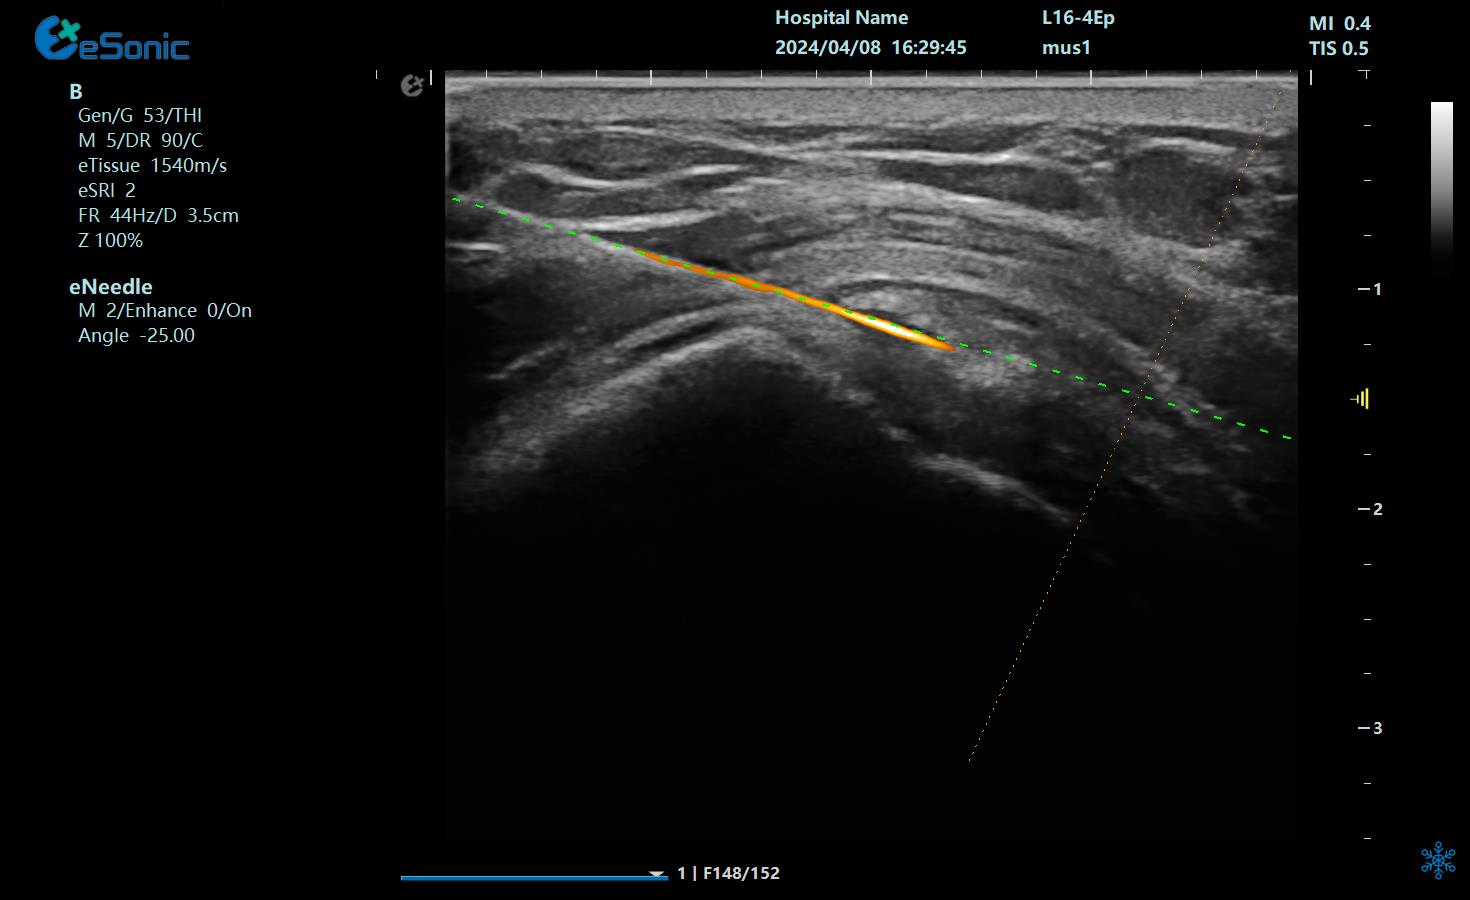

在超声图像中,穿刺针和钙化灶的显示都为强回声,常规的超声引导穿刺即使增强了穿刺针的显示仍不能有效地区分针尖和钙化灶,可能导致对穿刺部位的判断失误,往往比较依赖于医生的经验穿刺到钙化灶。

“Needle TsTM”登场新技术“秒 杀”钙化灶

hjc888黄金城官网医疗(ESI)Needle TsTM穿刺介入智能解决方案物理外挂三连:

1?? ?染色暴击?:给穿刺针穿上"荧光赛博战衣"(智能Map一键上色),钙化灶当场被标记成"通缉犯",超声屏秒变科幻大片!

2?? ?导航开挂?:针尖偏转0.1°?无磁导航立刻甩出"激光瞄准镜",实时画出钙化灶的投降路线图!

3?? ?精准降维?:针头化身"抽钙吸尘器",突突两下吸走顽固钙盐,手术时间比煮泡面还快!

针针5.png

治疗中使用穿刺针智能Map和无磁导航技术

在与钙化性肌腱炎的斗争中,精准是胜利的关键。hjc888黄金城官网医疗的“Needle TsTM”技术凭借其智能Map技术和无磁导航系统,成功解决了传统超声引导穿刺中的难题,让针尖与钙化灶清晰可辨。这种创新不仅提高了手术的成功率,更减少了患者的痛苦和恢复时间。如今,我们不再需要担心手术中的不确定性和风险,因为“Needle TsTM”为我们提供了前所未有的精准保障。它让那些曾经困扰我们的“小石头”无处遁形,让康复之路变得更加顺畅。